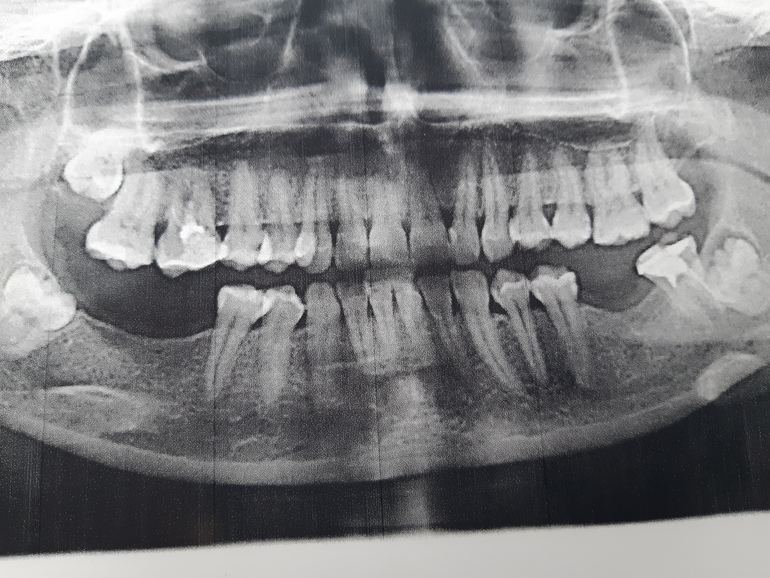

СтоматологияСитуация такая..простыла и стали боли сначала слевой стороны. ТОчно понять не могу сначала казалось что сверху боль больше ноющая редко колит бывает в ухо боль отдает ноющая. Потом словно больше снизу болит. Сделала панорамный снимок у меня снизу 7зуб плохо пролечен но говорят врят ли он боль даёт. Возможно что 8 задевает лицевой нерв. Вопрос такой может ли 8 внизу давать такие ощущения и сверху и в районе лица но боль в лице слабая как типо чуствую спазм сосудов. Либо это больше тройничный нерв но там как читаю боли будут сильные. Приклеплю снимок может есть врачи или кто так же сталкивался с таким

Тикие восьмерки очень часто портят соседние семёрки, в результате чего удалять приходится оба. Они ещё кисты могут давать. Скорее всего проблема с семёркой. Но и 8й тоже может, по личному опыту пульпит нижней восьмерки отзывается болью в поллица. Рекомендую сделать КТ, там лучше понятно.